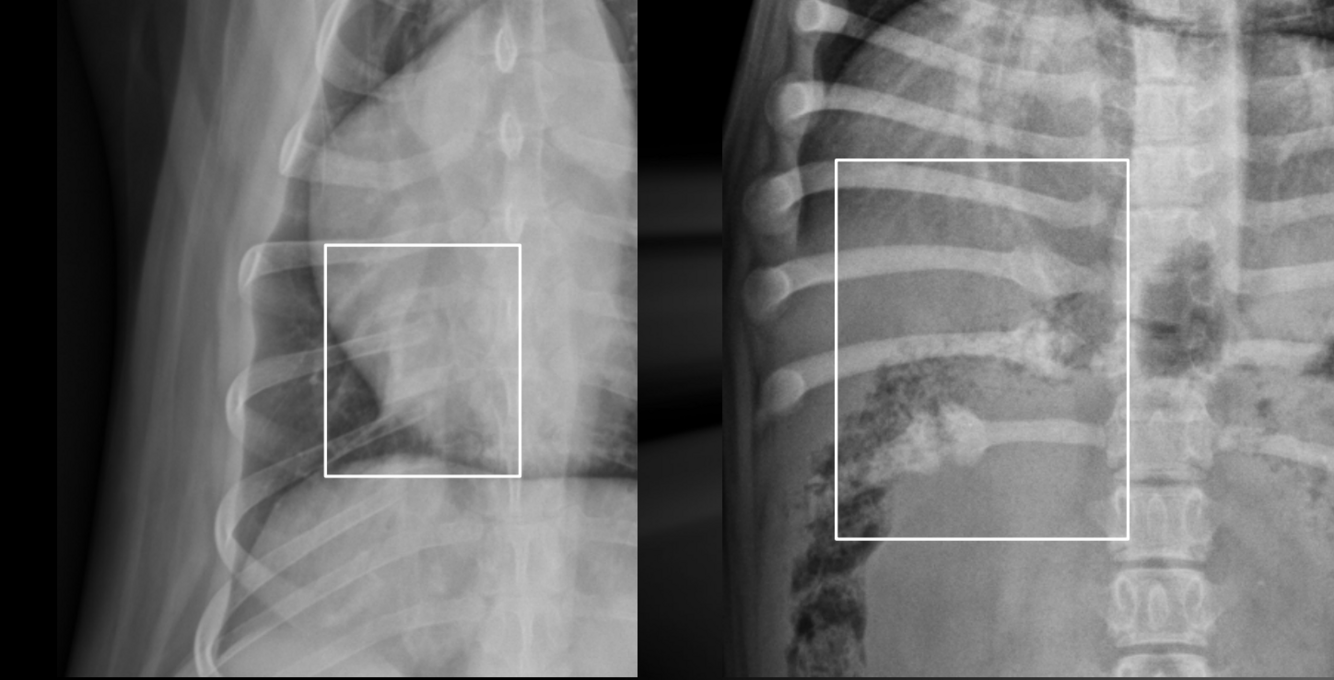

What is important regarding the ribs in these radiographs?

old dog; costal cartilages show irregular, exuberant mineralization